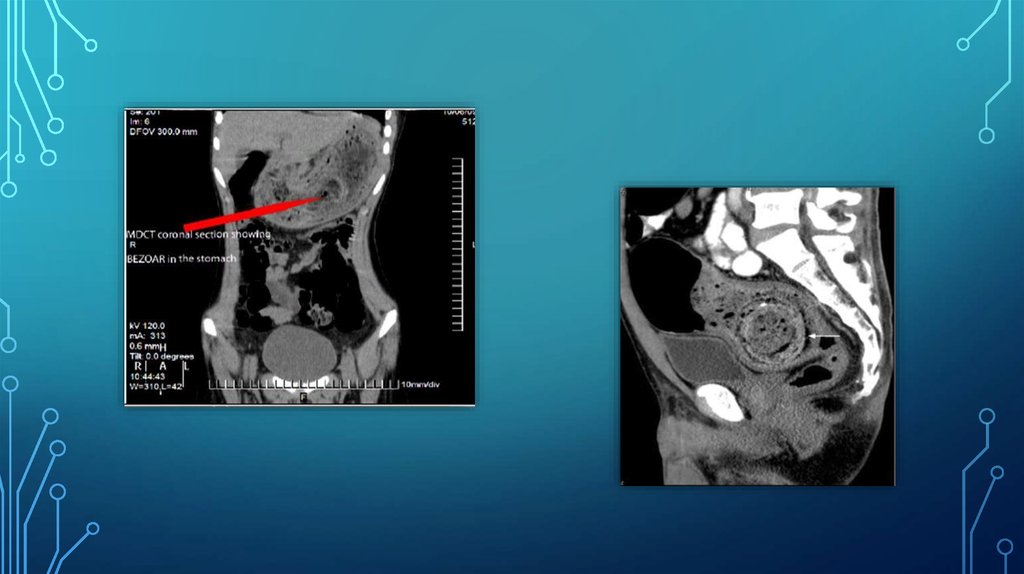

12. Кт-диагностика

КТ-ДИАГНОСТИКА